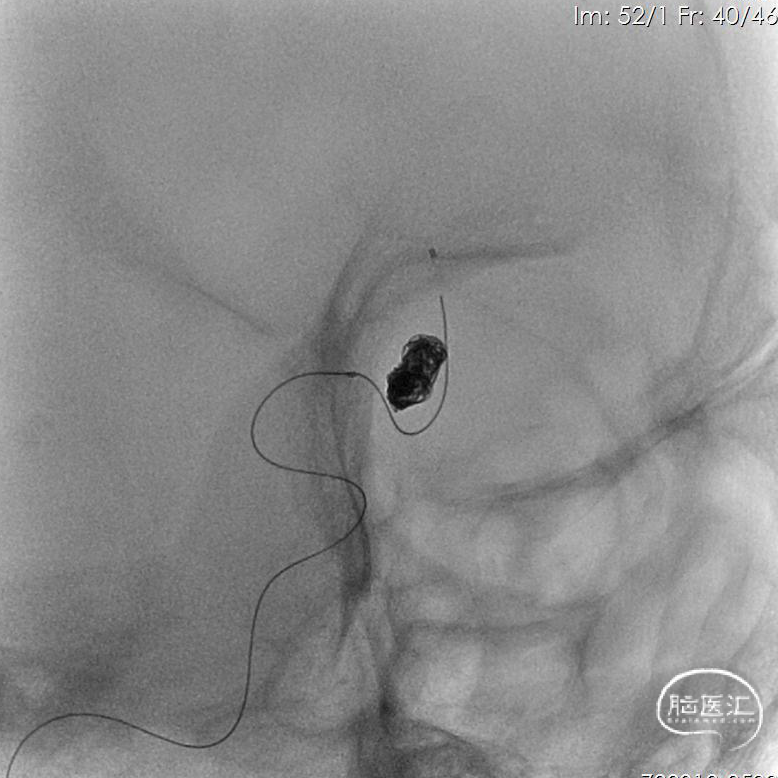

5、双微导管分区填塞动脉瘤。

6、填圈期间动态造影监测左侧大脑前动脉血流有无影响。

7、在瘤颈处可见可疑血栓影。

8、左侧大脑前动脉血流变慢。

9、动脉给予替罗非班后,左侧大脑前动脉血流未见好转。

10、将瘤颈口的微导管撤出后,左侧大脑前动脉血流较前略有好转。

11、反复造影观察后血流速度仍然减慢,造影见少量弹簧圈突入前交通动脉。

12、超选左侧大脑前动脉跟进微管,可见路径迂曲。

13、支架置入后左侧大脑前动脉血流好转。